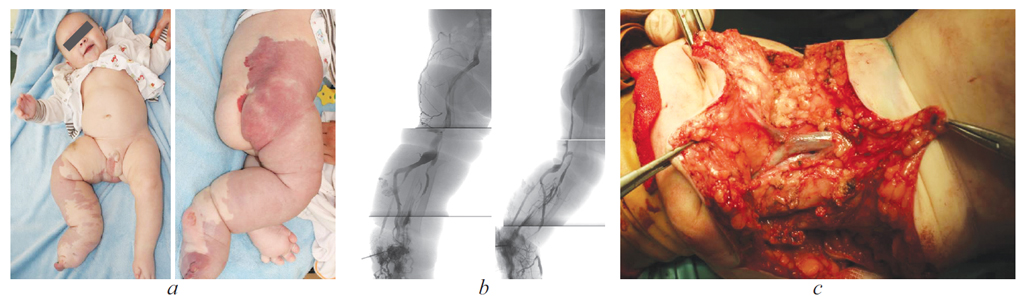

Выполнена внутрикостная флебография правой нижней конечности (рис. 1) — отмечается аплазия, гипоплазия, аневризматические расширения вен голени и подколенного венозного сегмента, отсутствует контрастирование подвздошно-бедренного венозного сегмента справа, основной отток крови идет через систему эмбриональных вен по заднее-латеральной поверхности голени и бедра (седалищная девиация).

Рис. 1. Пациент К.В., 1 год: дисплазия магистральных вен, эмбриональный тип, крайне тяжелая степень: а&— внешний вид, b&— восходящая флебография, c&— эмбриональная вена в подкожной клетчатке подколенной области (этап операции)

Fig. 1. Patient K.V., 1 years old: dysplasia of the main veins, embryonic type, extremely severe: а&– appearance, b&– ascending phlebography, c&– embryonic vein in the subcutaneous tissue of the popliteal region (operation stage)